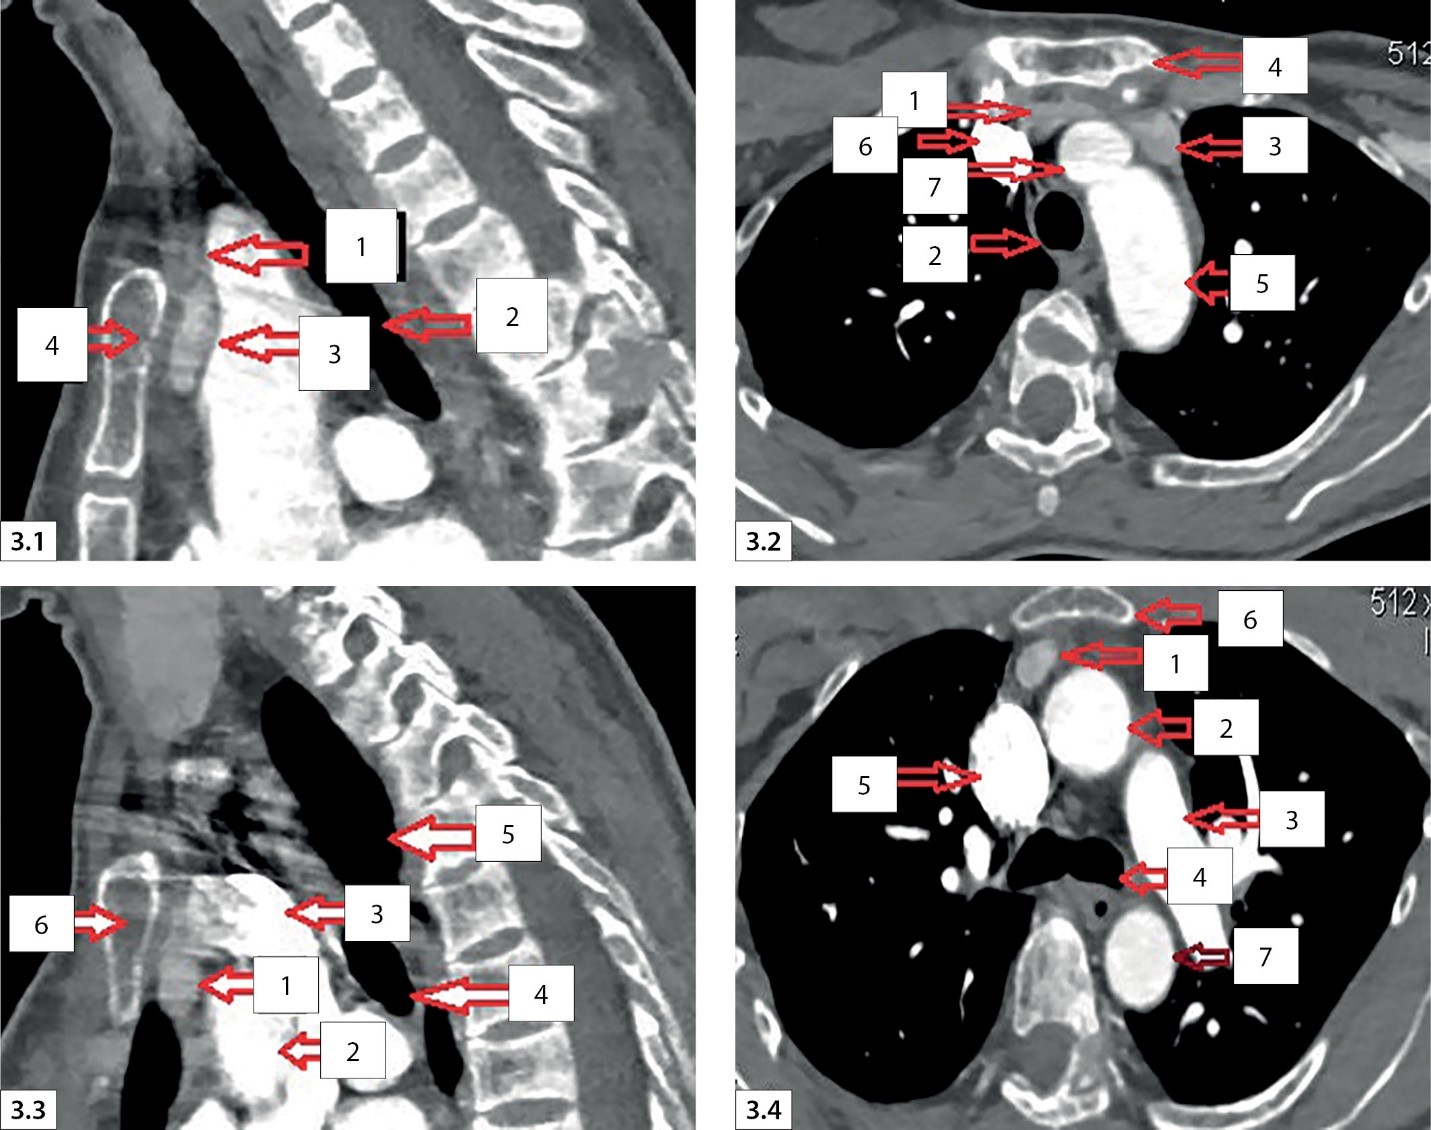

4. Рисунок 3. МСКТ. Мультиспиральная компьютерная томография шеи с ангиографией с внутривенным контрастированием. | |

Посмотреть

(263KB)